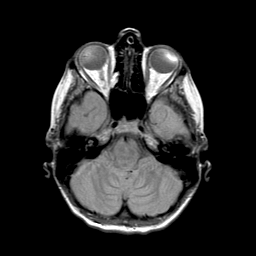

Metastatic bronchogenic carcinoma: proton density-weighted MR -- Slice #4

[Home][Help][Clinical] Slice 4